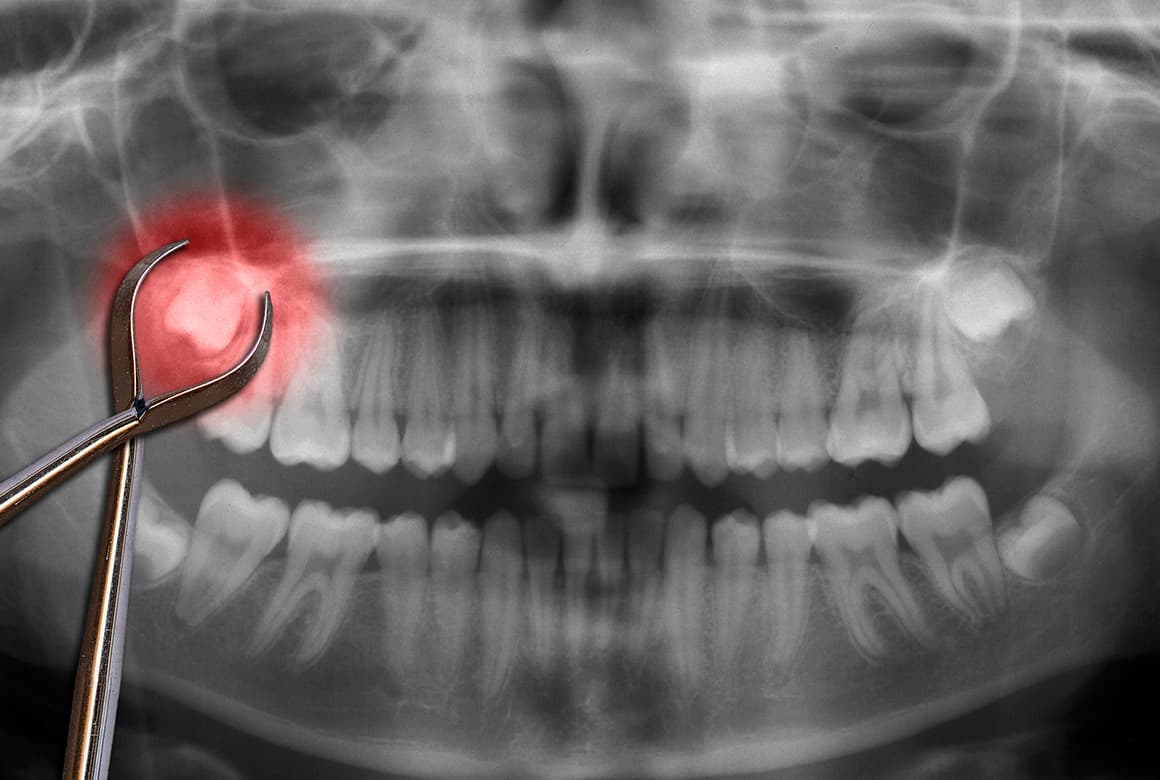

口腔内の状態を知るための入念な検査

親知らずの抜歯後には、神経麻痺や後出血ほか合併症などのリスクがあるのが事実です。それらを防止するため、当院では親知らずがどのように生えているかを確かめる事前のCT撮影による精密検査を怠りません。

その後、検査結果をもとに現在の状態や抜歯の必要性などを丁寧にご説明。患者さんにご納得いただいてから、治療に入ります。